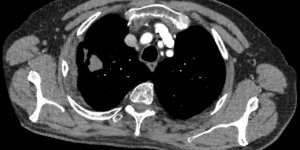

Lung Cancer | Pancoast

Published on Feb 16, 2021

71 male First appointment 3 Month history of Right rhomboid pain. Aggravated by shoulder movements. Struggles to get to sleep and occasionally wakes up. No P+N or numbness. No dizziness, diplopia, dysarthria, dysphagia, drop attacks, nausea. Exam Slight winging right scapula. Full shoulder ROM Full shoulder strength Provisional Diagnosis [...] Read more